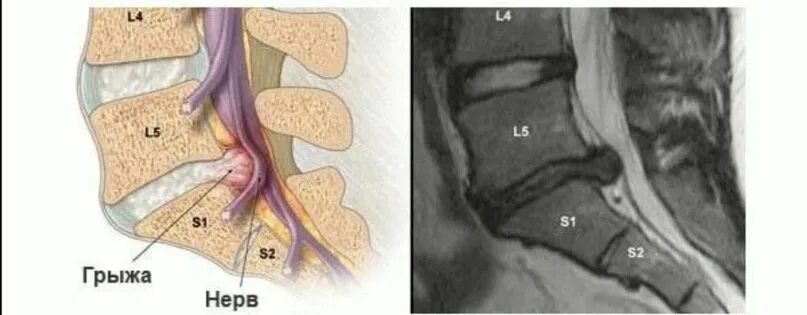

L5 s1 срединная грыжа